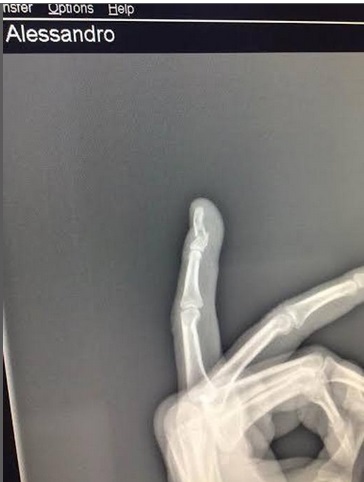

Onorato su Facebook ha postato alcune foto in cui si vedono le escoriazioni, la lastra con il dito rotto e una corsia di ospedale ed ha commentato così la vicenda:

“Ormai non è sicuro neanche andare in Campidoglio a rappresentare i cittadini che finisci in ospedale perché aggredito e minacciato. Una volta c’era la sinistra del popolo e degli operai, oggi c’è quella dei centri sociali che ti aggredisce se la richiami alle sue responsabilità . Grazie per il mignolo rotto. Povera Roma. Poveri noi. ‪#‎PeciolaVergogna”.